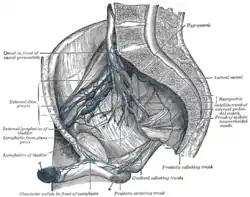

Iliopelvic glands, lateral view. (Hypogastric labeled at upper right.) | |

The internal iliac lymph nodes (or hypogastric) surround the internal iliac artery and its branches (the hypogastric vessels), and receive the lymphatics corresponding to the distribution of the branches of it, i. e., they receive lymphatics from all the pelvic viscera, from the deeper parts of the perineum, including the membranous and cavernous portions of the urethra, and from the buttock and back of the thigh. The internal iliac lymph nodes also drain the superior half of the rectum, above the pectinate line.[1][2]